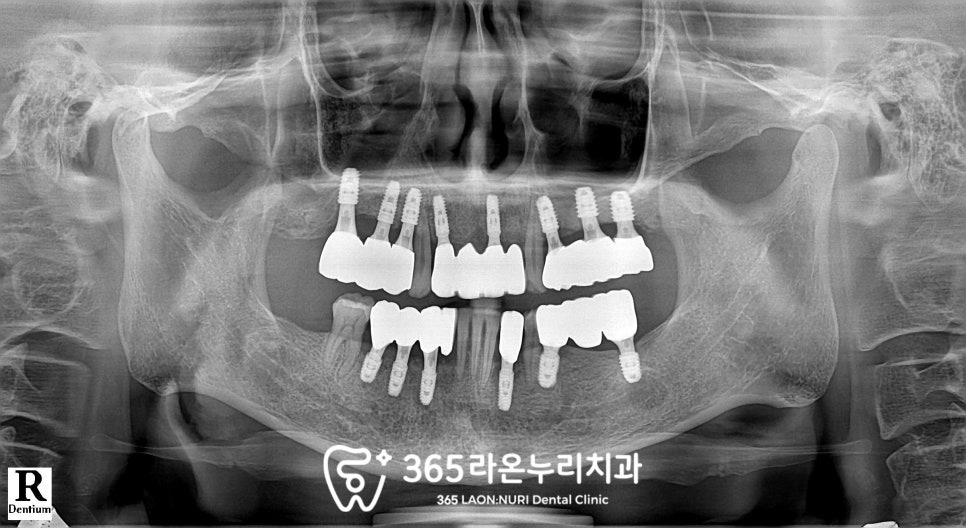

파노라마를 찍게 되는데

이 과정에서 치조골의 높이와

치아 뿌리 끝 염증까지 확인할 수 있습니다.

엑스레이를 통해 살펴보니

치조골의 높이가 상당히 낮아져있으며

위아래가 제대로 물리는 곳이 없을 만큼

교합도 불안정합니다.

전반적으로 골소실이 매우 심하고

뼈도 많이 녹아있습니다.

보이는 것처럼 아무래도 좌우위아래

모두 식립이 필요하다 보니